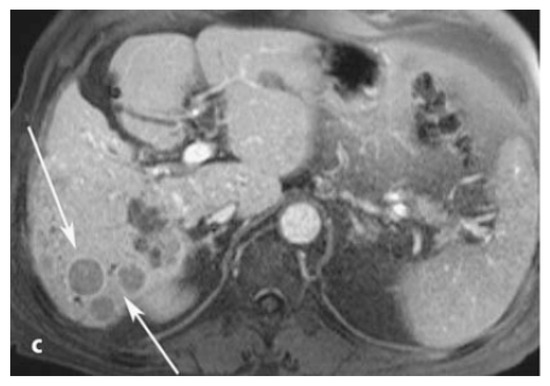

- El-Gazzar, M.F.; Kohla, M.A.S.; El-Sakhawy, M.M.; Husseiny, M.M.; Yousef, R.R.H.; El-Shorbagy, S.H. Use of gadobenate dimeglumine dynamic MRI for detection of early hepatocellular carcinoma in atypical hepatic focal lesions. Hepatoma Res. 2017, 3, 123–128. [Google Scholar] [CrossRef][Green Version]

- Grazioli, L.; Bondioni, M.P.; Faccioli, N.; Gambarini, S.; Tinti, R.; Schneider, G.; Kirchin, M. Solid focal liver lesions: Dynamic and late enhancement patterns with the dual phase contrast agent gadobenate dimeglumine. J. Gastrointest. Cancer 2010, 41, 221–232. [Google Scholar] [CrossRef] [PubMed]

- Jeong, W.K.; Kim, Y.K.; Song, K.D.; Choi, D.; Lim, H.K. The MR imaging diagnosis of liver diseases using gadoxetic acid: Emphasis on hepatobiliary phase. Clin. Mol. Hepatol. 2013, 19, 360–366. [Google Scholar] [CrossRef] [PubMed]